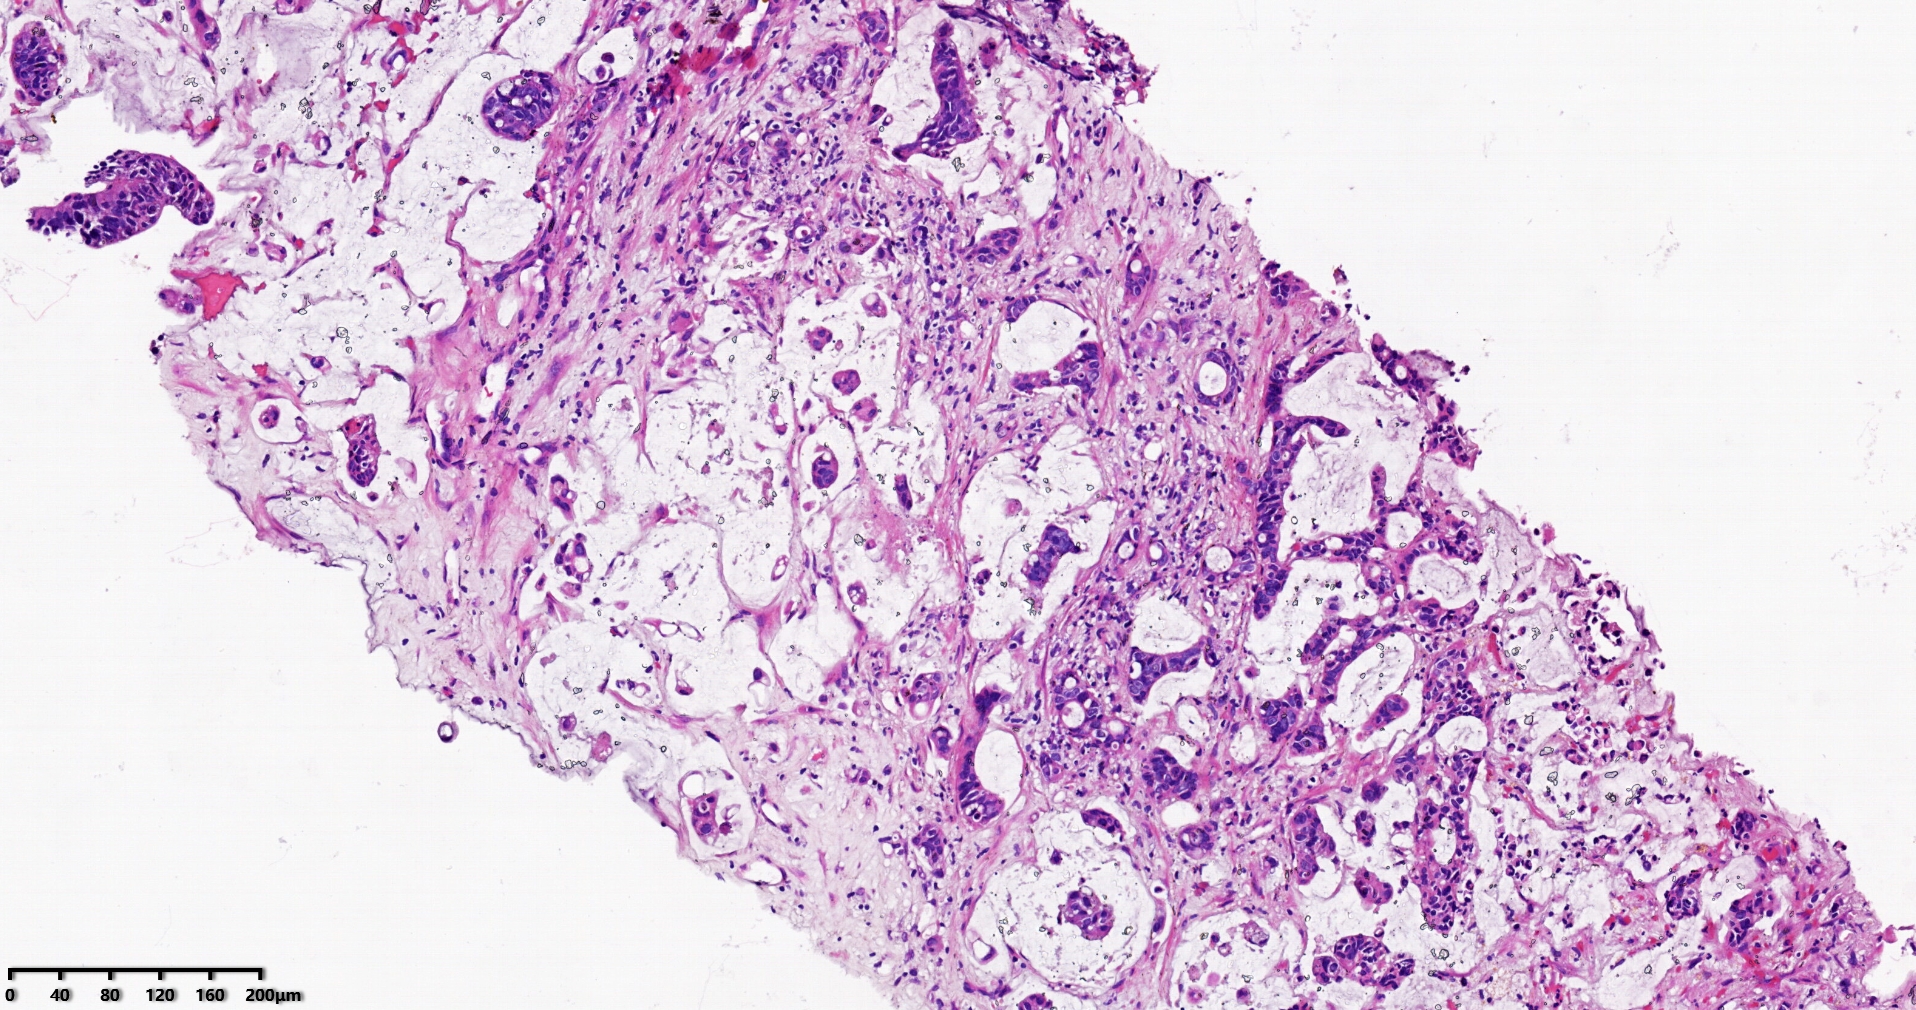

标本名称肝脏穿刺

大体所见灰白灰红色穿刺活检组织两条,长1.7-1.9cm,直径0.1-0.2cm。

考虑符合:肝内胆管癌

考虑转移性黏液腺癌,消化道来源可能,建议做免疫组化,排除胆管源性。